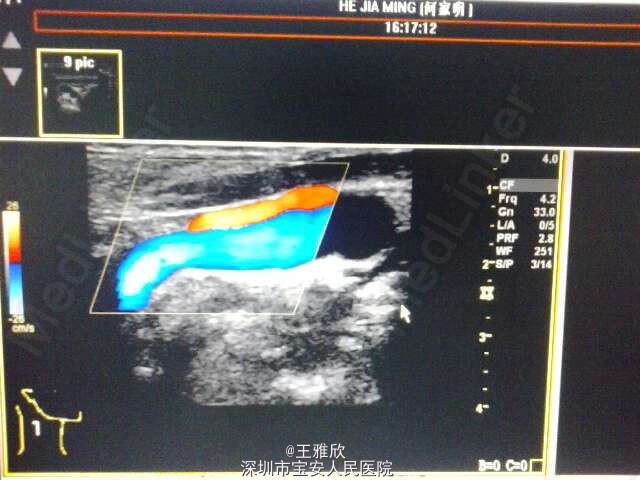

体格检查无特殊,辅助检查:头颅CT:1、轻度脑白质疏松症 2、右侧上颌窦及双侧轻度炎症。头颅MR提示:双侧放射冠、半卵圆中心多发腔隙性脑梗塞,脑动脉硬化。双侧颈动脉+椎动脉:1、双侧颈动脉硬化性改变伴双侧斑块形成,未见明显闭塞,2、双侧椎动脉行走弯曲,左侧椎动脉血流阻力增高,超声心动过图:主动脉硬化、室间隔稍厚,主动脉瓣轻度反流,二尖瓣轻度反流,左室舒张功能降低。